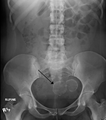

A very large (9 cm) fibroid of the uterus which is causing pelvic congestion syndrome as seen on CT

A very large (9 cm) fibroid of the uterus which is causing pelvic congestion syndrome as seen on ultrasound